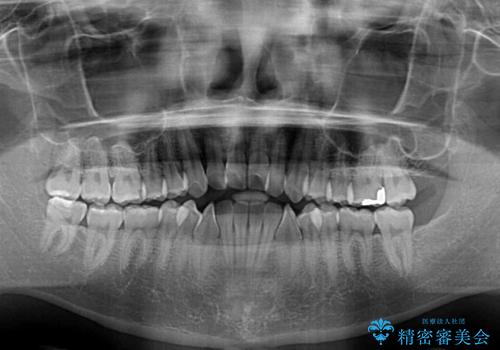

オープンバイトをインビザラインで矯正治療

- 前歯の開咬を気にして来院された患者様です。

開咬の治療は、前歯を閉じるように動かすとともに、上下臼歯を圧下(骨内にめり込ませる)させることで進めて行きます。

インビザラインは臼歯の圧下を効果的に行えるため、インビザラインを用いて矯正治療を行うこととしました。